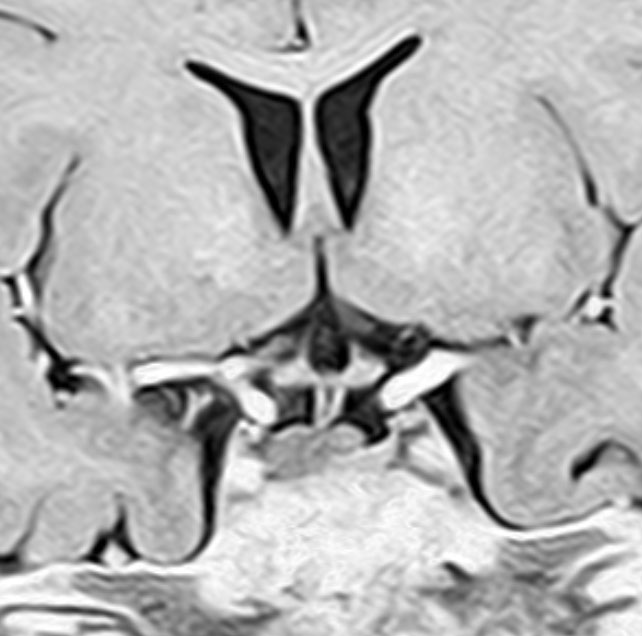

血清HCG-beta 4.5mIUで,下のMRIに見られるように第3脳室(視床下部)のグリオーマ(毛様細胞性星細胞腫)と見間違うような腫瘍でした。下垂体柄は太くなっていないし下垂体のサイズも普通です。もちろん水頭症もありませんので,開頭手術で生検をしてgerminomaの診断を得ました。

上のMRIで視神経交叉が腫大しているのが解りますが,下のMRI CISS画像では更に明らかです,左右の視神経と視交差と視索が腫大していました。視力を計ったら,右0.6,左1.5でいびつな視野欠損がありました。腫瘍はのう胞形成しながら左の視床下部から大脳基底核にも浸潤していました。

6年以上発ちますが再発はありません。右の画像のように視神経交叉のサイズは正常化しました。下垂体は左に偏っているので,おそらく右側の下垂体にも腫瘍があったのでしょう。汎下垂体機能低下症はありますが,副腎皮質ホルモンの補充は必要なくて,部分的下垂体機能低下症です。この幼児期の低身長が視床下部性であったのか,下垂体前葉機能低下によるものであったのかは不明です。治療後に高ナトリウム血症になる傾向があり,思春期早発症のために成長ホルモンを使用しながらLH-RHアナログを使うという事もしていますから,おそらく視床下部性のGHDであったのでしょう。